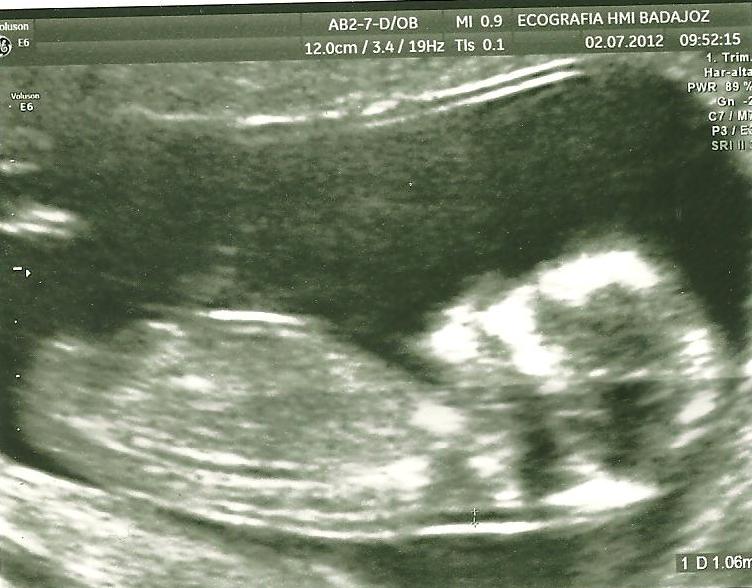

Ecografía de 13 semanas

Así llegue a la ecografía con miedo. En la sala de espera hubo un buen presagio porque la chica que atendieron antes de mi salió con una sonrisa espléndida. Llegó mi turno y yo solo escuché: TODO BIEN. Son unas palabras mágicas que te relajan y desde entonces ya puedes disfrutar admirando una y otra vez la foto del bebe de 7 centímetros más guapo del mundo. Vale, mide 6,8, pero ya sabéis que las madres somos muy exageradas y yo ya estoy mostrando síntomas de exceso de orgullo. Como imaginaréis también salí del hospital con una sonrisa radiante.

Tras el miedo parezco una boba que anda por el mundo mostrando la ecografía y diciéndole a todo el mundo: “tiene nariz”. La gente me mira como si fuese imbécil (pensarán: ¿por qué no iba a tenerla?), pero me da igual. Al menos mi familia me apoya en la locura colectiva de la llegada del bebé y mi madre incluso ha mandado imprimir la ecografía y la tiene enmarcada.